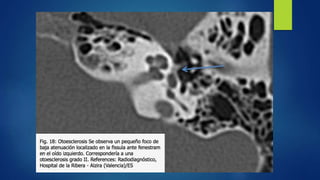

 TAC: El hallazgo radiológico fundamental es un foco lítico, de baja

atenuación en cápsula ótica .Aparece un área desmineralización, de baja

atenuación.